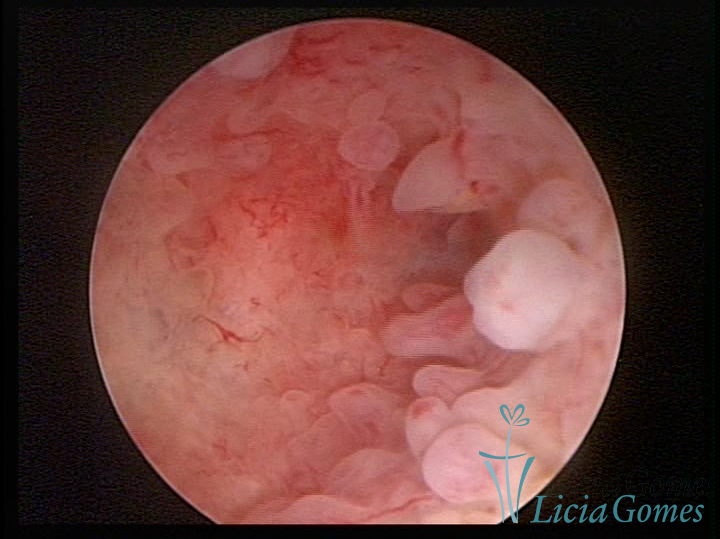

Este pode apresentar uma gama variável de aspectos macroscópicos, com aspecto pseudopolipoide; lembrando tecido cerebroide ou com reação deciduoide;a vascularização superficial é mais evidente e com vasos em formatos de saca-rolha ou espirais visualizando também a vascularização com atípias, com aumento do calibre dos vasos superficiais, pode ser encontrado também tecido em necrose, poderá haver um pequenos dendritos (papilomatoso).